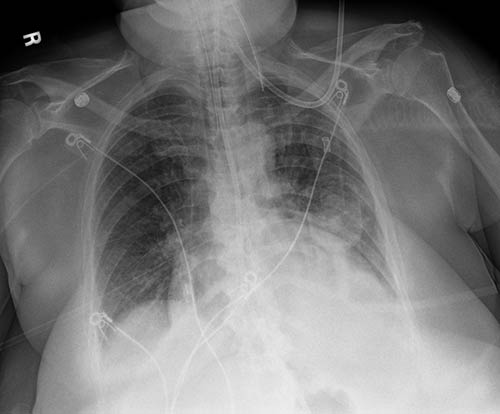

确保一次曝光。球管和插管增强创建相配影像,并采用优化的处理,以便更清晰、更轻松地可视化外周穿刺中心静脉插管和球管。它增强了正确置放球管和插管并保持在原位的信心。